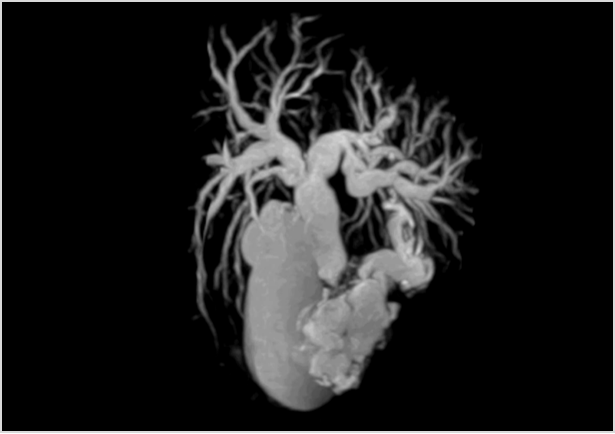

心血管系统方向

3.0T核磁依然可以做到无需造影剂全身血管成像,例如上下肢动静脉成像及颅脑动静脉成像,背景组织抑制好,有利于小血管显示。心脏扫描,可以从各方向对心脏进行扫描成像,有利于心脏疾病诊断。